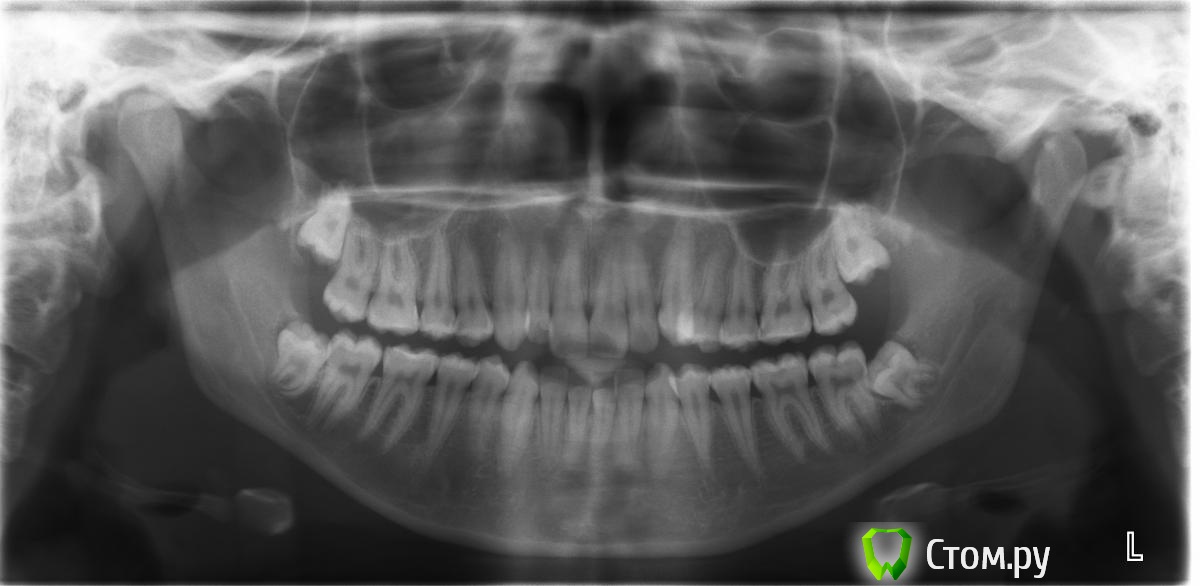

ShkipeR Опубликовано 4 сентября, 2014 Поделиться Опубликовано 4 сентября, 2014 Пациентка 18 лет.Каков план лечения и на какой системе Вы бы посоветовали?Заранее спасибо? Ссылка на комментарий

ShkipeR Опубликовано 8 сентября, 2014 Автор Поделиться Опубликовано 8 сентября, 2014 Сейчас будем идти на санацию и удаление восьмерок Ссылка на комментарий

Monkey Опубликовано 25 сентября, 2014 Поделиться Опубликовано 25 сентября, 2014 А я бы начала с удаления 8-х и СПА на верхнюю челюсть, хорошо бы расширила и сразу брекеты. Ссылка на комментарий